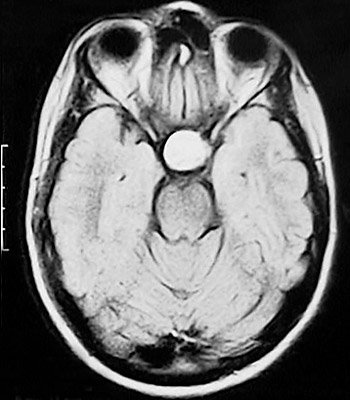

The T1 weighted MRI scan in axial view here demonstrates a macroadenoma of the pituitary that is bright with gadolinium enhancement. Pituitary adenomas may be functional, with secretion of a hormone that first produces symptoms.